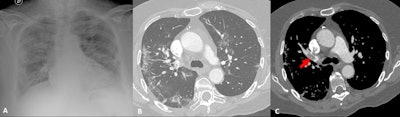

Italy

Italy was quite hard hit, said Dr. Nicola Sverzellati, head of the radiology unit at the University Hospital of Parma. The country's first patient, a 38-year-old man, presented at an emergency department in Codogno in February with acute respiratory distress syndrome. Only a few weeks later, the government locked Codogno and neighboring villages down. As the virus spread through the country, clinicians across Italy began tracking chest CT features of COVID-19, including ground-glass opacities, multilobe involvement, bilateral distribution, and posterior involvement.